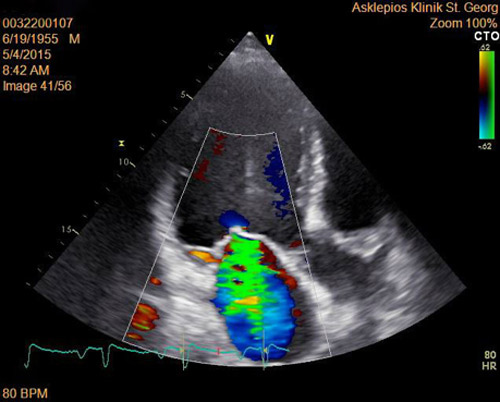

Mit einem entsprechenden Gerät, genannt „Doppler-Ultraschall“, kann der Blutfluss im Herzen sogar farbig dargestellt werden (Abb. 1). So lassen sich Herzklappendefekte und ihre Auswirkungen sehr deutlich darstellen. Auch die Pumpleistung (Ejektionsfraktion, auch Auswurffraktion genannt) des Herzens kann bestimmt werden.